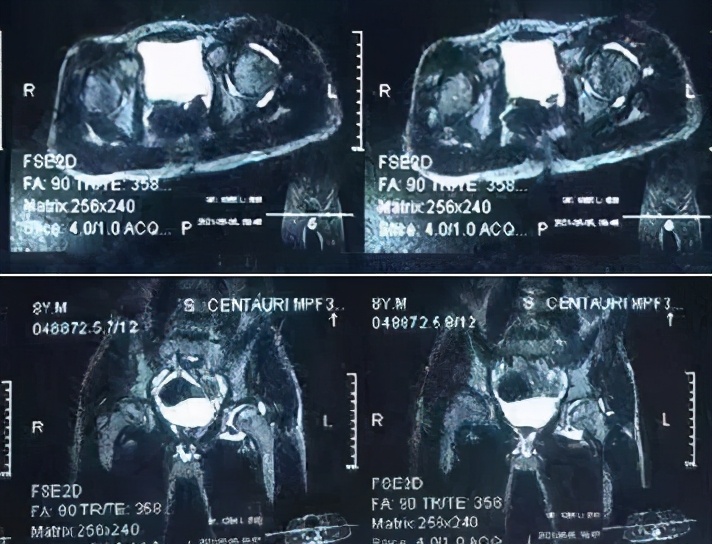

(2)MRI检查 磁共振检查显示患侧髋关节间隙增宽和关节腔积液,并较线平片显示更加清晰。同时能显示髋关节内是否存在软组织占位。MRI显示在髋臼和股骨头软骨之间的滑膜组织在T1W1呈中等信号,T2W1呈高信号。(3)B型超声检查 患髋股骨颈颈前间隙较健侧明显增宽,双侧差值>1mm。股骨颈颈前间隙,即股骨颈骨膜表面至关节囊外缘(关节囊与髂腰肌的分界线)之间的最大距离。